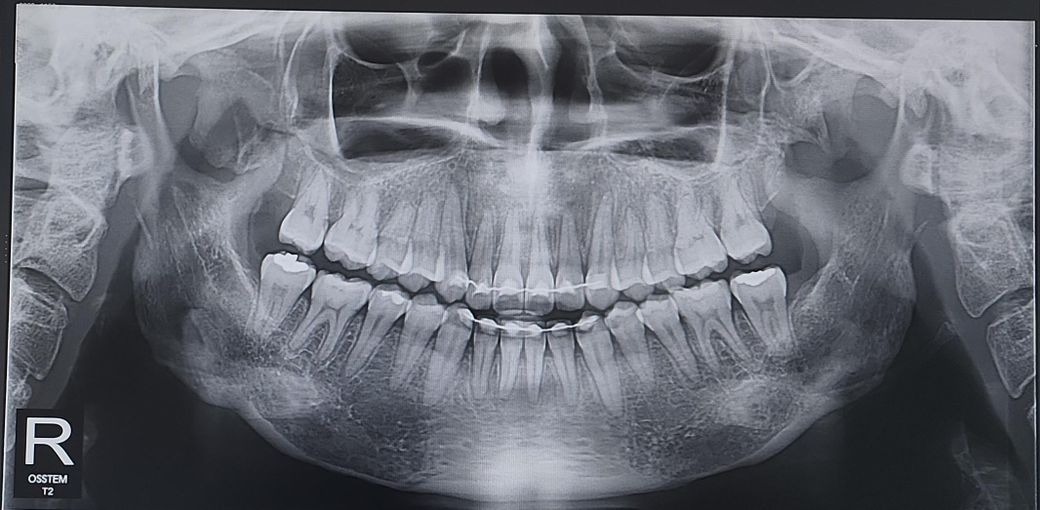

혹시 이게 교정기를 뗀지 얼마 안되어서 느끼는 단순 시림인지, 아니면 예상되는 문제가 있는지 궁금합니다. 파노라마 사진 상 안보이는 충치가 있는 건지도 같이 봐주시면 감사하겠습니다. 오른쪽 아래 첫번째 큰 어금니에요!

• 1번 째 사진

특별히 문제가 보이진 않는 거 같습니다. 시린 증상이 일시적일 수도 있으니 지켜보셔도 될 듯 합니다.

작은 사진을 다시 찍어보고 확인을 해봐야 알겟지만, 아래 앞니 아래쪽에 염증이 잇는거 같습니다.

엑스레이상 충치는 없으나 해당 치아와 잇몸뼈 사이의 인대(치주인대)가 긴장상태입니다 원인은 불명확하나 인대가 정상으로 회복될 수 있도록 당분간은 딱딱하거나 질긴음식 아예 피하시기 바랍니다